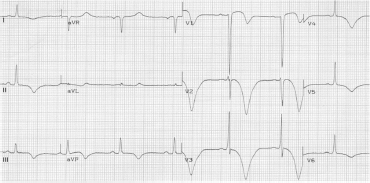

Paciente de 70 anos do sexo masculino, hipertenso, diabético e tabagista, dá entrada no pronto-socorro com queixa de dor torácica em aperto de forte intensidade há 1 hora.

Realizado o seguinte ECG:

Você, que está em um centro com hemodinâmica disponível, optou pela realização de cineangiocoronariografia de emergência com provável angioplastia primária.

Nesse caso, a dose de ataque de clopidogrel que deve ser dada a esse paciente é de